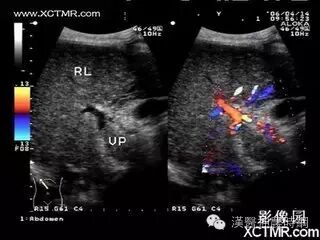

1.超声检查  B超检查用于肝癌诊断具有无损伤、无放射损害、简便、价廉、敏感度高、可重复性等优点。它可显示肿瘤的大小、形状、部位、肿瘤与血管的关系以及肝静脉、门静脉有无癌栓等,其诊断符合率可达90%。B超可检出1~2cm的小肝癌,最小直径为0.5~0.7cm。文献报道高分辨力B超对0.5~2.0cm的肝内微小灶的发现率较高,但定性诊断的准确率仅为58%。近年国内外均有人采用超声对比剂,如铁或钆等行声学造影,有助于定性诊断和确定病灶大小。原发性肝癌B超图像常显示肝体积增大,病变向肝表面隆起,周围常有声晕等。其回声可表现为低回声型、高回声型和混合回声型。小肝癌常呈低回声型,大肝癌或呈高回声,或高低回声混合,并可见中心坏死液化的无回声区。B超检查可因肺、胃等器官遮盖存在盲区,造成遗漏病变,如右膈下、左外叶上段等。微小病变位于肝实质深部并伴有严重肝硬化时,常难以辨认。另外与操作者的经验和检查是否细致均有关。